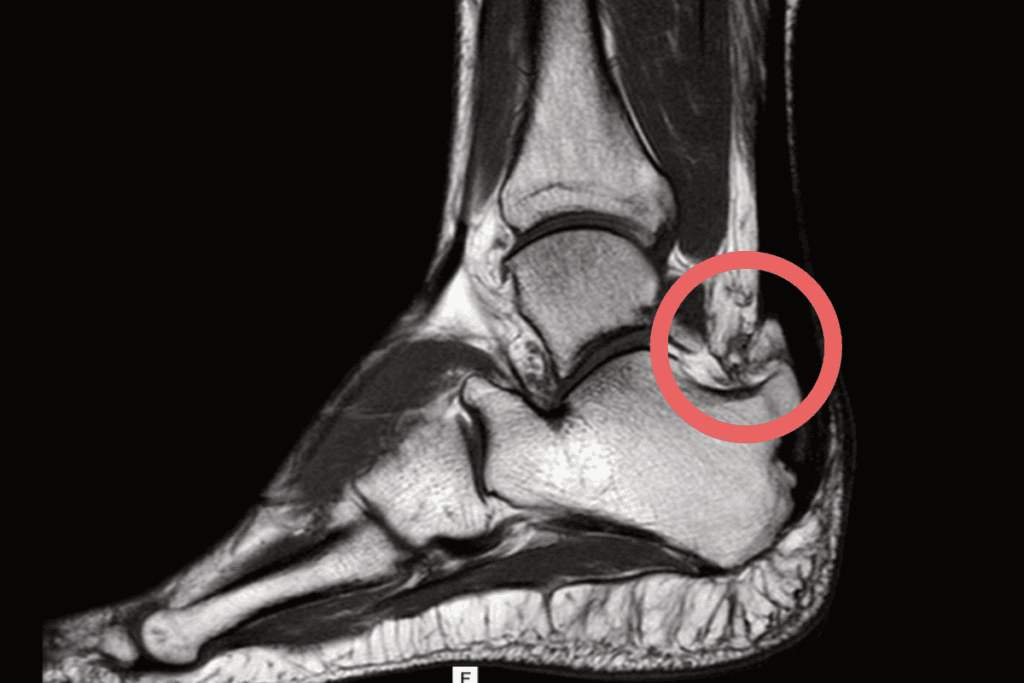

- stopniowej utraty elastyczności i zwiększonej podatności na urazy ścięgna Achillesa a z czasem powolnego nadrywania się przyczepu ścięgna Achillesa do kości piętowej,

- przewlekłego zapalenia kaletki ścięgna Achillesa,

- podrażnienia i degeneracji przyczepu ścięgna Achillesa,

- obrzęku i włóknienia tkanek miękkich otaczających guz piętowy oraz powstawania charakterystycznych zwapnień i “ostróg”,

- stopniowej utraty elastyczności i zwiększonej podatności na urazy ścięgna Achillesa a z czasem powolnego nadrywania się przyczepu ścięgna Achillesa do kości piętowej.

- podawanie osocza bogatopłytkowego/czynników wzrostu lub komórekwielopotencjalnych – ma na celu poprawę gojenia się ścięgna Achillesa ale takie zabiegi muszą iść w parze z prawidłową fizjoterapią;

- reinsercja ścięgna Achillesa – w przypadkach znacznych zmian degeneracyjnych i zagrożenia całkowitego zerwania.